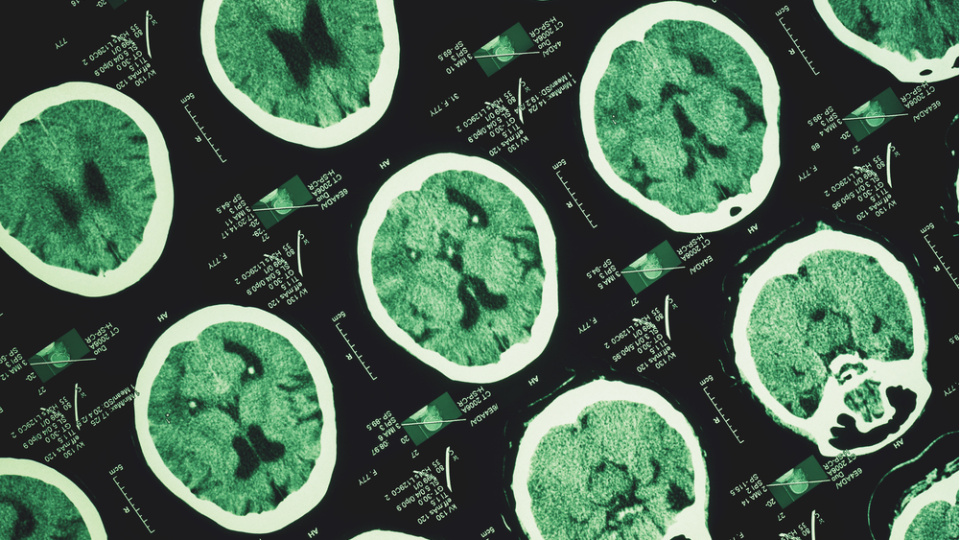

Türk Nöroloji Derneğinden, 13 Mart Dünya Uyku Günü dolayısıyla yapılan açıklamada, uykunun, nörolojik açıdan beynin en yoğun mesai yaptığı zamanlardan biri olduğu belirtildi.

Açıklamada, son yıllarda keşfedilen glimfatik sistemin, uyku sırasında beynin adeta temizlik moduna geçtiğini ortaya koyduğu, gün içinde biriken metabolik atıkların ve potansiyel nörotoksik maddelerin bu süreçte temizlendiği ifade edildi.

Bu mekanizmanın bozulmasının, Alzheimer gibi nörodejeneratif hastalıklarla ilişkili olabileceğine dikkat çekilen açıklamada, "Uyku yalnızca enerji toplamak değil, beynin kendini koruması ve yenilemesi için zorunlu bir süreçtir" değerlendirmesi yapıldı.